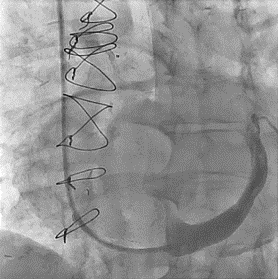

The authors report the case of a 79-year-old male patient who benefited from the implantation of a coronary sinus reducer (CSR) (Reducer; Neovasc, Inc.) in the management of typical angina with mild exertion with optimal medical treatment.

02/07/2024